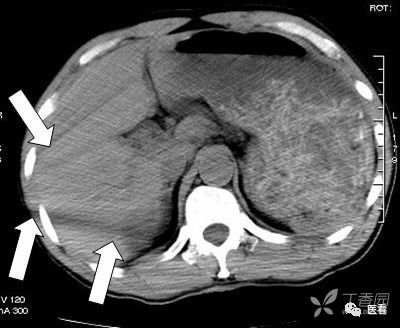

CT造影中可能出现的假象——涡流

这里强调一个CT造影中可能产生的假象——涡流

也就是团注(高压注射器快速注入)的碘对比剂与血液没有混匀之前,没有对比剂的血液呈低密度(红箭头),有对比剂的血流呈高密度,不要误认为是血栓